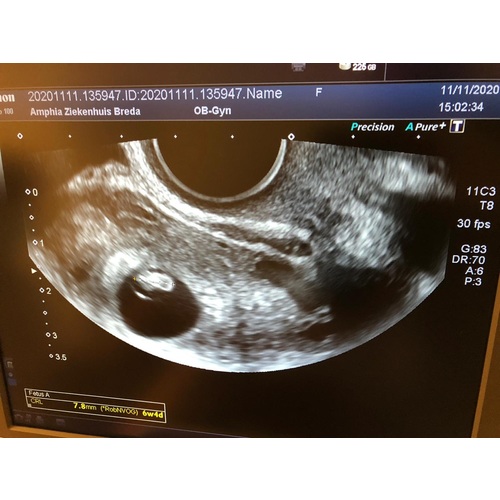

Volgens de arts 6+4, volgens m’n eigen berekening was ik al een week verder

Alles in orde en een kloppend hartje 🙏🏻